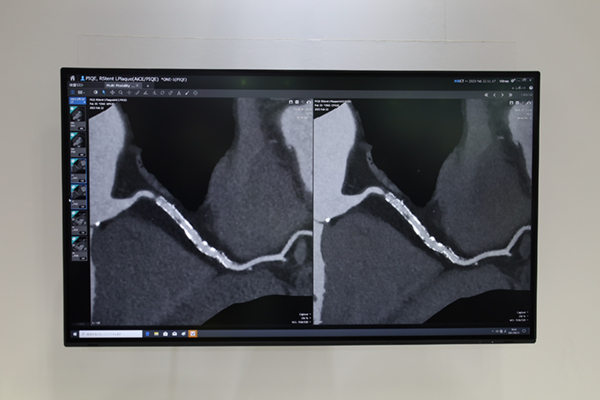

キヤノンメディカルシステムズ社は,80列マルチスライスCT「Aquilion Serve」と高精細CT「Aquilion Precision」を実機展示し,高精細とAIを用いた自動化技術を軸に展示を行った。Aquilion Serveでは,ガントリ内のカメラを利用したポジショニングサポート機能の「Automatic Camera Positioning」,低線量で撮影された三次元データを利用して撮影範囲の自動設定を行う「Automatic Scan Planning」,表示させるレイアウトをプリセットできる「Automatic Hanging Layout」など検査をサポートする機能を搭載しているが,これらの機能を新たに「INSTINX」のブランド名で統合した。INSTINXは,世界中の医療機関で行われた臨床テストを基にワークフローの細部にまで改良を加えて,直感的な操作性を実現し効率性と一貫性を追究する新たなワークフローである。また,Aquilion Precisionでは,AiCEのパラメータに脳血管用(Brain CTA),中内耳用(Inner Ear),骨・軟部用(Bone)が加わり,AiCEが全身領域に適用可能になったことを紹介した。さらに,ADCT「Aquilion ONE / PRISM Edition」に搭載された超解像技術「Precise IQ Engine(PIQE)」については,微小石灰化プラークや冠動脈ステントの描出など,心臓CT領域で高精細画像が得られることを多くの臨床データでアピールした。

超解像DLRのPIQEによりADCTで撮影した冠動脈ステントの描出能が向上